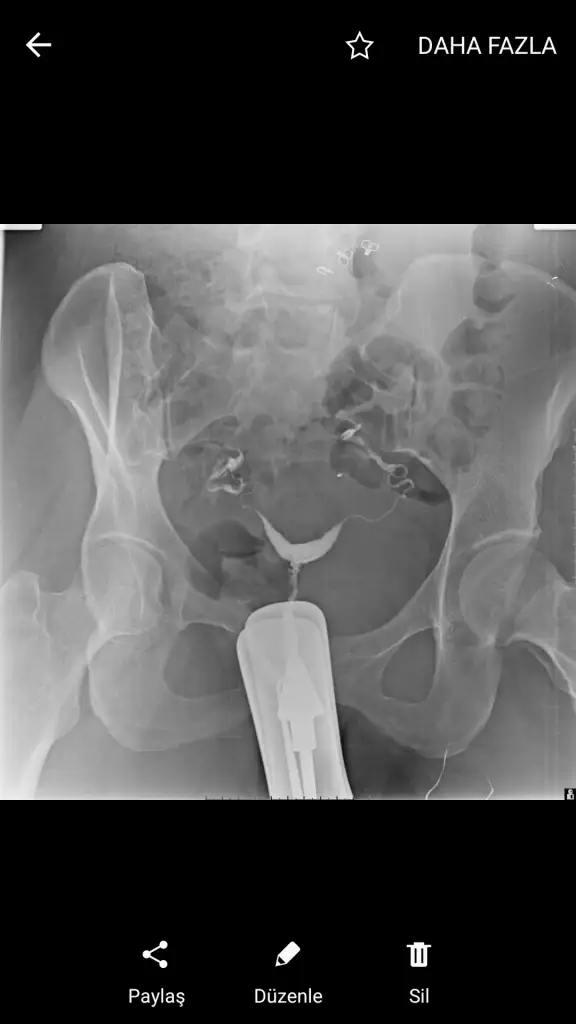

Rahim filmim bu😕

Eklentiler

• Screenshot_20210227-235248.webp

Screenshot_20210227-235248.webp

12,5 KB · Görüntüleme: 179